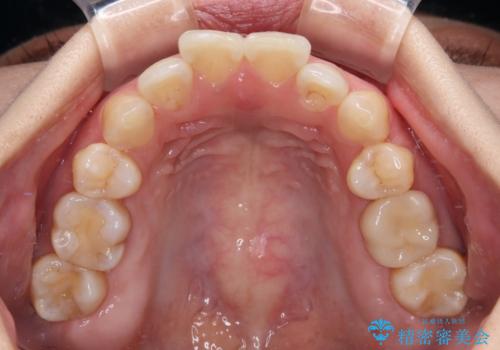

- 上下前歯の後戻りを気にして来院された患者様です。

インビザラインでの治療を希望されていて、デコボコの程度が中等度であり、安価なパッケージにて対応可能と判断されたため、インビザライン・モデレートを用いて矯正治療を行うこととしました。